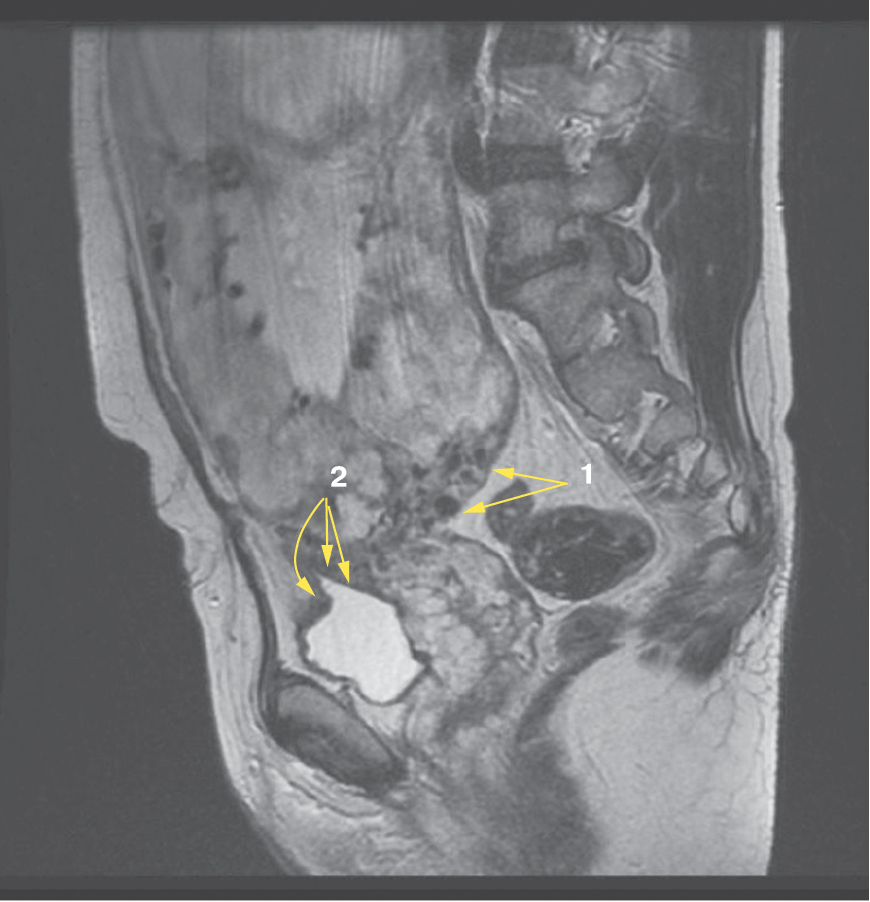

Также стоит выделить особый тип плацентарной гиперваскуляризации, а именно включение в плацентарной ткани изменений по типу «обнаженного сосуда» (рис. 1, 2). Мы провели анализ встречаемости данного признака среди наших пациентов. Любопытным наблюдением явилось то, что данный симптом в нашей выборке встречался только при наличии placenta percreta – 6 случаев, а именно при поражении параметриев, и не встречался при плацентарной инвазии, ограниченной миометрием. «Мостовидные сосуды» были менее специфичны, тем не менее, их наличие также сопровождало тяжелые формы врастания, обусловленные более глубокой инвазией ворсин хориона, – 8 случаев.

Рис. 1. МРТ placenta percreta, симптом «обнаженного сосуда»

Рис. 2. МРТ placenta percreta, симптом «обнаженного сосуда»

Является ли симптом «обнаженного сосуда» патогномоничным для параметральной инвазии или нет, еще предстоит выяснить; однако в ходе исследования установлена его связь с частотой гистерэктомий в группах с наличием симптома «обнаженного сосуда», что, вероятно, обусловлено мощной сосудистой сетью коллатералей и неоангиогенезом. Во всех случаях обнаружения данного признака впоследствии была выполнена вынужденная гистерэктомия (рис. 3–6, пациентка Н., 37 лет).

Рис. 5. Корональная проекция МРТ. 1 – интрамуральная гиперваскуляризация; 2- измененный контур мочевого пузыря

Рис. 6. Корональная проекция МРТ. 1 – обнаженный сосуд; 2 – интрамуральная гиперваскуляризация; 3 – гиперваскуляризация плаценты